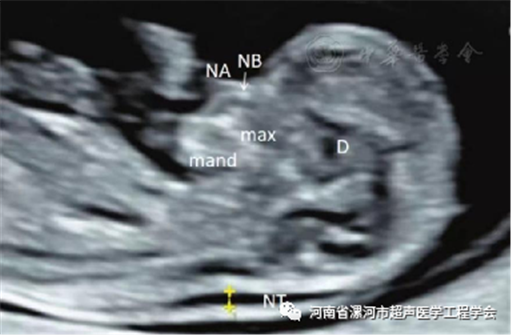

01什么是NT检查?NT(Nuchal Translucency),即颈项透明层,指胎儿颈项背部皮肤层与筋膜层之间软组织的最大厚度,反映胎儿颈后皮下组织内淋巴液体积聚的厚度。NT检查就是在超声图像上测量此透明层厚度。

02NT值的测量规范

1、胎龄在11~13+6周,胎儿头臀长在45~84mm之间。

2、胎儿正中矢状切面测量。

3、胎儿在自然姿势状态下测量( 不能过伸或过屈)。

4、尽可能放大图像,只显示头部及上部胸腔,轻微移动游标,测量结果改变为0.1mm。

5、游标卡尺放在定义NT厚度的界线上。

6、在距离最宽处测量NT厚度。

7、要区分胎儿皮肤与羊膜。

8、必须为颈项透明层内部边界的边缘垂直测量。

9、如果出现胎儿脐带绕颈,这时测量NT会增大,在这种情况下,在脐带上下方测的NT数值会不同,推荐使用两者的平均值。

10、至少测量3次,并取其最大测量值。

因此,我们想要取得标准的NT测量结果,是需要相应的胎儿标准切面和规范的测量手法。胎儿颈部过屈、伸展都不符合标准切面,所以NT检查过程中可能经常会出现“位置不好出去走走再来检查吧”等情况。03NT值多少为异常?NT厚度随着孕周的增大而增加,因此,不同孕周测量NT不能用同一个标准来判断。目前多数学者认为NT厚度超过第95百分位可认为NT增厚。多种文献报道,NT≥3mm时,约10%的胎儿存在重大畸形,而NT≥6mm时,约90%的胎儿存在重大畸形。